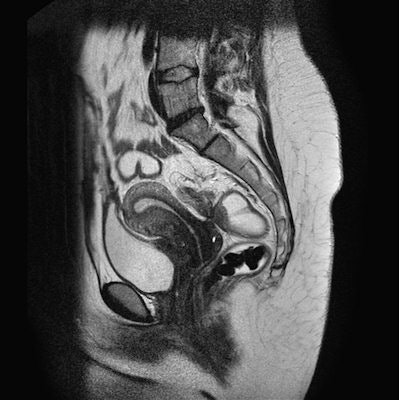

HAMBURG - MRI can be used to detect endometriomas, difficult-to-detect cells from the lining of the uterus found outside the uterine cavity, and also guide surgical intervention, according to a presentation from the 95th congress of the German Society of Radiology (DRK), 28-31 May.

Every tenth woman suffers from endometriosis, which can cause infertility and pain. Endometriomas are difficult to detect, but MRI can help, according to a study conducted by Dr. Julia Wenzel from the department of diagnostic and interventional radiology at Giessen University Hospital in Marburg, Germany.

Endometriomas may be found in places such as on the ovaries, on the bowel wall, or on the bladder. Removal by surgical intervention is the standard treatment.

"Endometriomas can take on a variety of phenotypes, including cysts and adhesions, which adds to the difficulty of identifying them in MR images," Wenzel said.

MRI proved to be particularly reliable in the detection of endometriomas in the rear abdominal cavity and, with a detection rate of 90%, on the colon. This is significant because endometrial tissue is frequently overlooked in that region. In a number of cases, endometriomas grow into the colon wall and are difficult for the surgeon to see.

The method was somewhat less successful for the front abdominal cavity, in particular for the bladder and the uterine wall. MRI proved less helpful in detecting very small endometriomas.